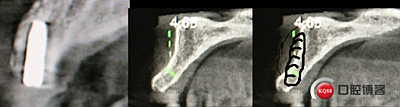

“以修復(fù)為導(dǎo)向”,在前牙種植體中心點就是未來牙冠舌側(cè)窩位置。那這個病例植體的方向和位置就只能是下圖右側(cè)這樣了。很明顯植體根尖部分要穿出唇側(cè)倒凹的。怎么辦?翻大瓣植骨蓋膜減張縫合?不!可以不翻瓣,大家仔細看看下圖右圖我畫的那條細細的弧線,是不是跟原來唇側(cè)凹陷的骨面成為左右對稱的兩條弧,也就是說骨膜從原來唇側(cè)凹陷骨面上剝離然后放到左側(cè)我畫的那條弧線那里根本不需要減張,這兩條弧線之間也就是唇側(cè)凹陷處放上骨粉,骨膜不會增加張力。不知道大家看明白了沒有。

術(shù)后4個月X光片。